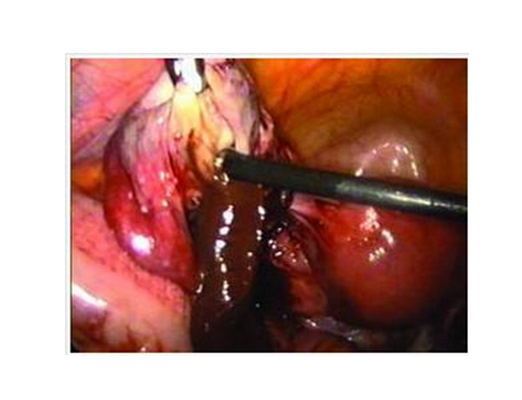

子宮頸糜爛圖片

宮頸糜爛 (8)

宮頸糜爛 (9)

宮頸糜爛 (56)

宮頸糜爛 (57)

宮頸糜爛 (58)

宮頸糜爛 (59)

宮頸糜爛 (6)

宮頸糜爛 (60)

宮頸糜爛 (7)

宮頸糜爛 (40)

宮頸糜爛 (41)

宮頸糜爛 (42)

宮頸糜爛 (43)

宮頸糜爛 (44)

宮頸糜爛 (45)

宮頸糜爛 (46)

宮頸糜爛 (47)

宮頸糜爛 (48)

宮頸糜爛 (49)

宮頸糜爛 (5)